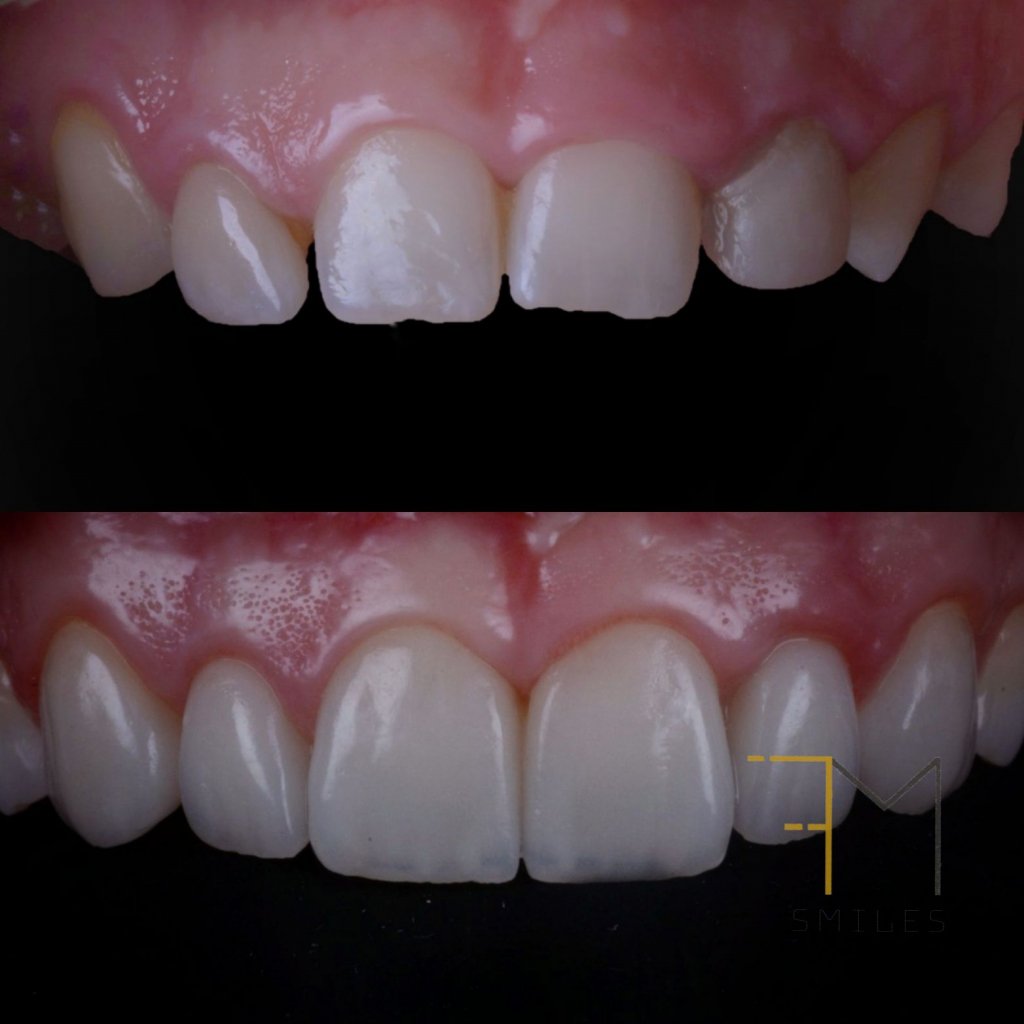

Me cuenta que ya en pasado, a los 18 años, se sometió a una ortodoncia y intentar enmascarar la microdoncia de los laterales con unas «carillas cerámicas». Esto era el resultado de dicho tratamiento: